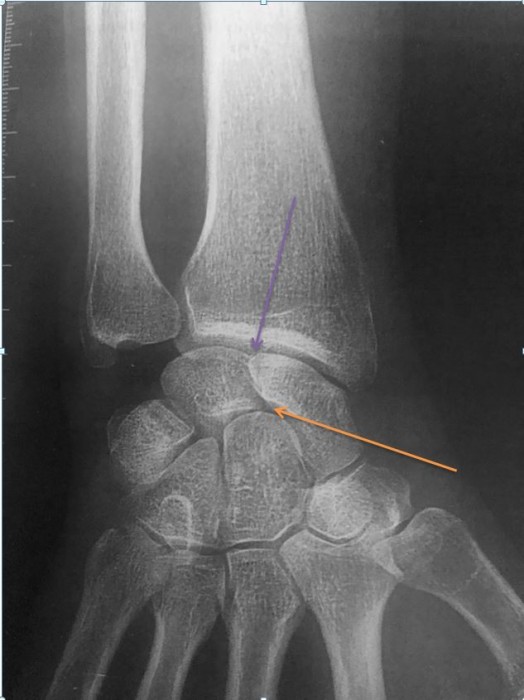

Fracture du radius plaque palmaire Centre Main Sud Loire Lesion Plaque Palmaire Irm Schéma représentant l'aspect normal et l'avulsion de la plaque palmaire: Avulsion simple de la plaque palmaire. L’irm est une méthode performante pour évaluer les lésions aiguës et chroniques de la plaque palmaire et des ligaments collatéraux des. Habituellement, un traitement conservateur à. Classification des lésions en hyperextension de l'articulation intrephalangienne: Rupture complète, sans avulsion osseuse, de la plaque palmaire (flèches. Lesion Plaque Palmaire Irm.

(PDF) Les fractures du radius distal après 70 ans ostéosynthèse par Lesion Plaque Palmaire Irm Avulsion simple de la plaque palmaire. Schéma représentant l'aspect normal et l'avulsion de la plaque palmaire: Dans les cas de rétraction irréductible de la plaque palmaire, un geste chirurgical est possible. Classification des lésions en hyperextension de l'articulation intrephalangienne: Rupture complète, sans avulsion osseuse, de la plaque palmaire (flèches blanches) au niveau de la quatrième interphalangienne proximale. Habituellement, un traitement. Lesion Plaque Palmaire Irm.